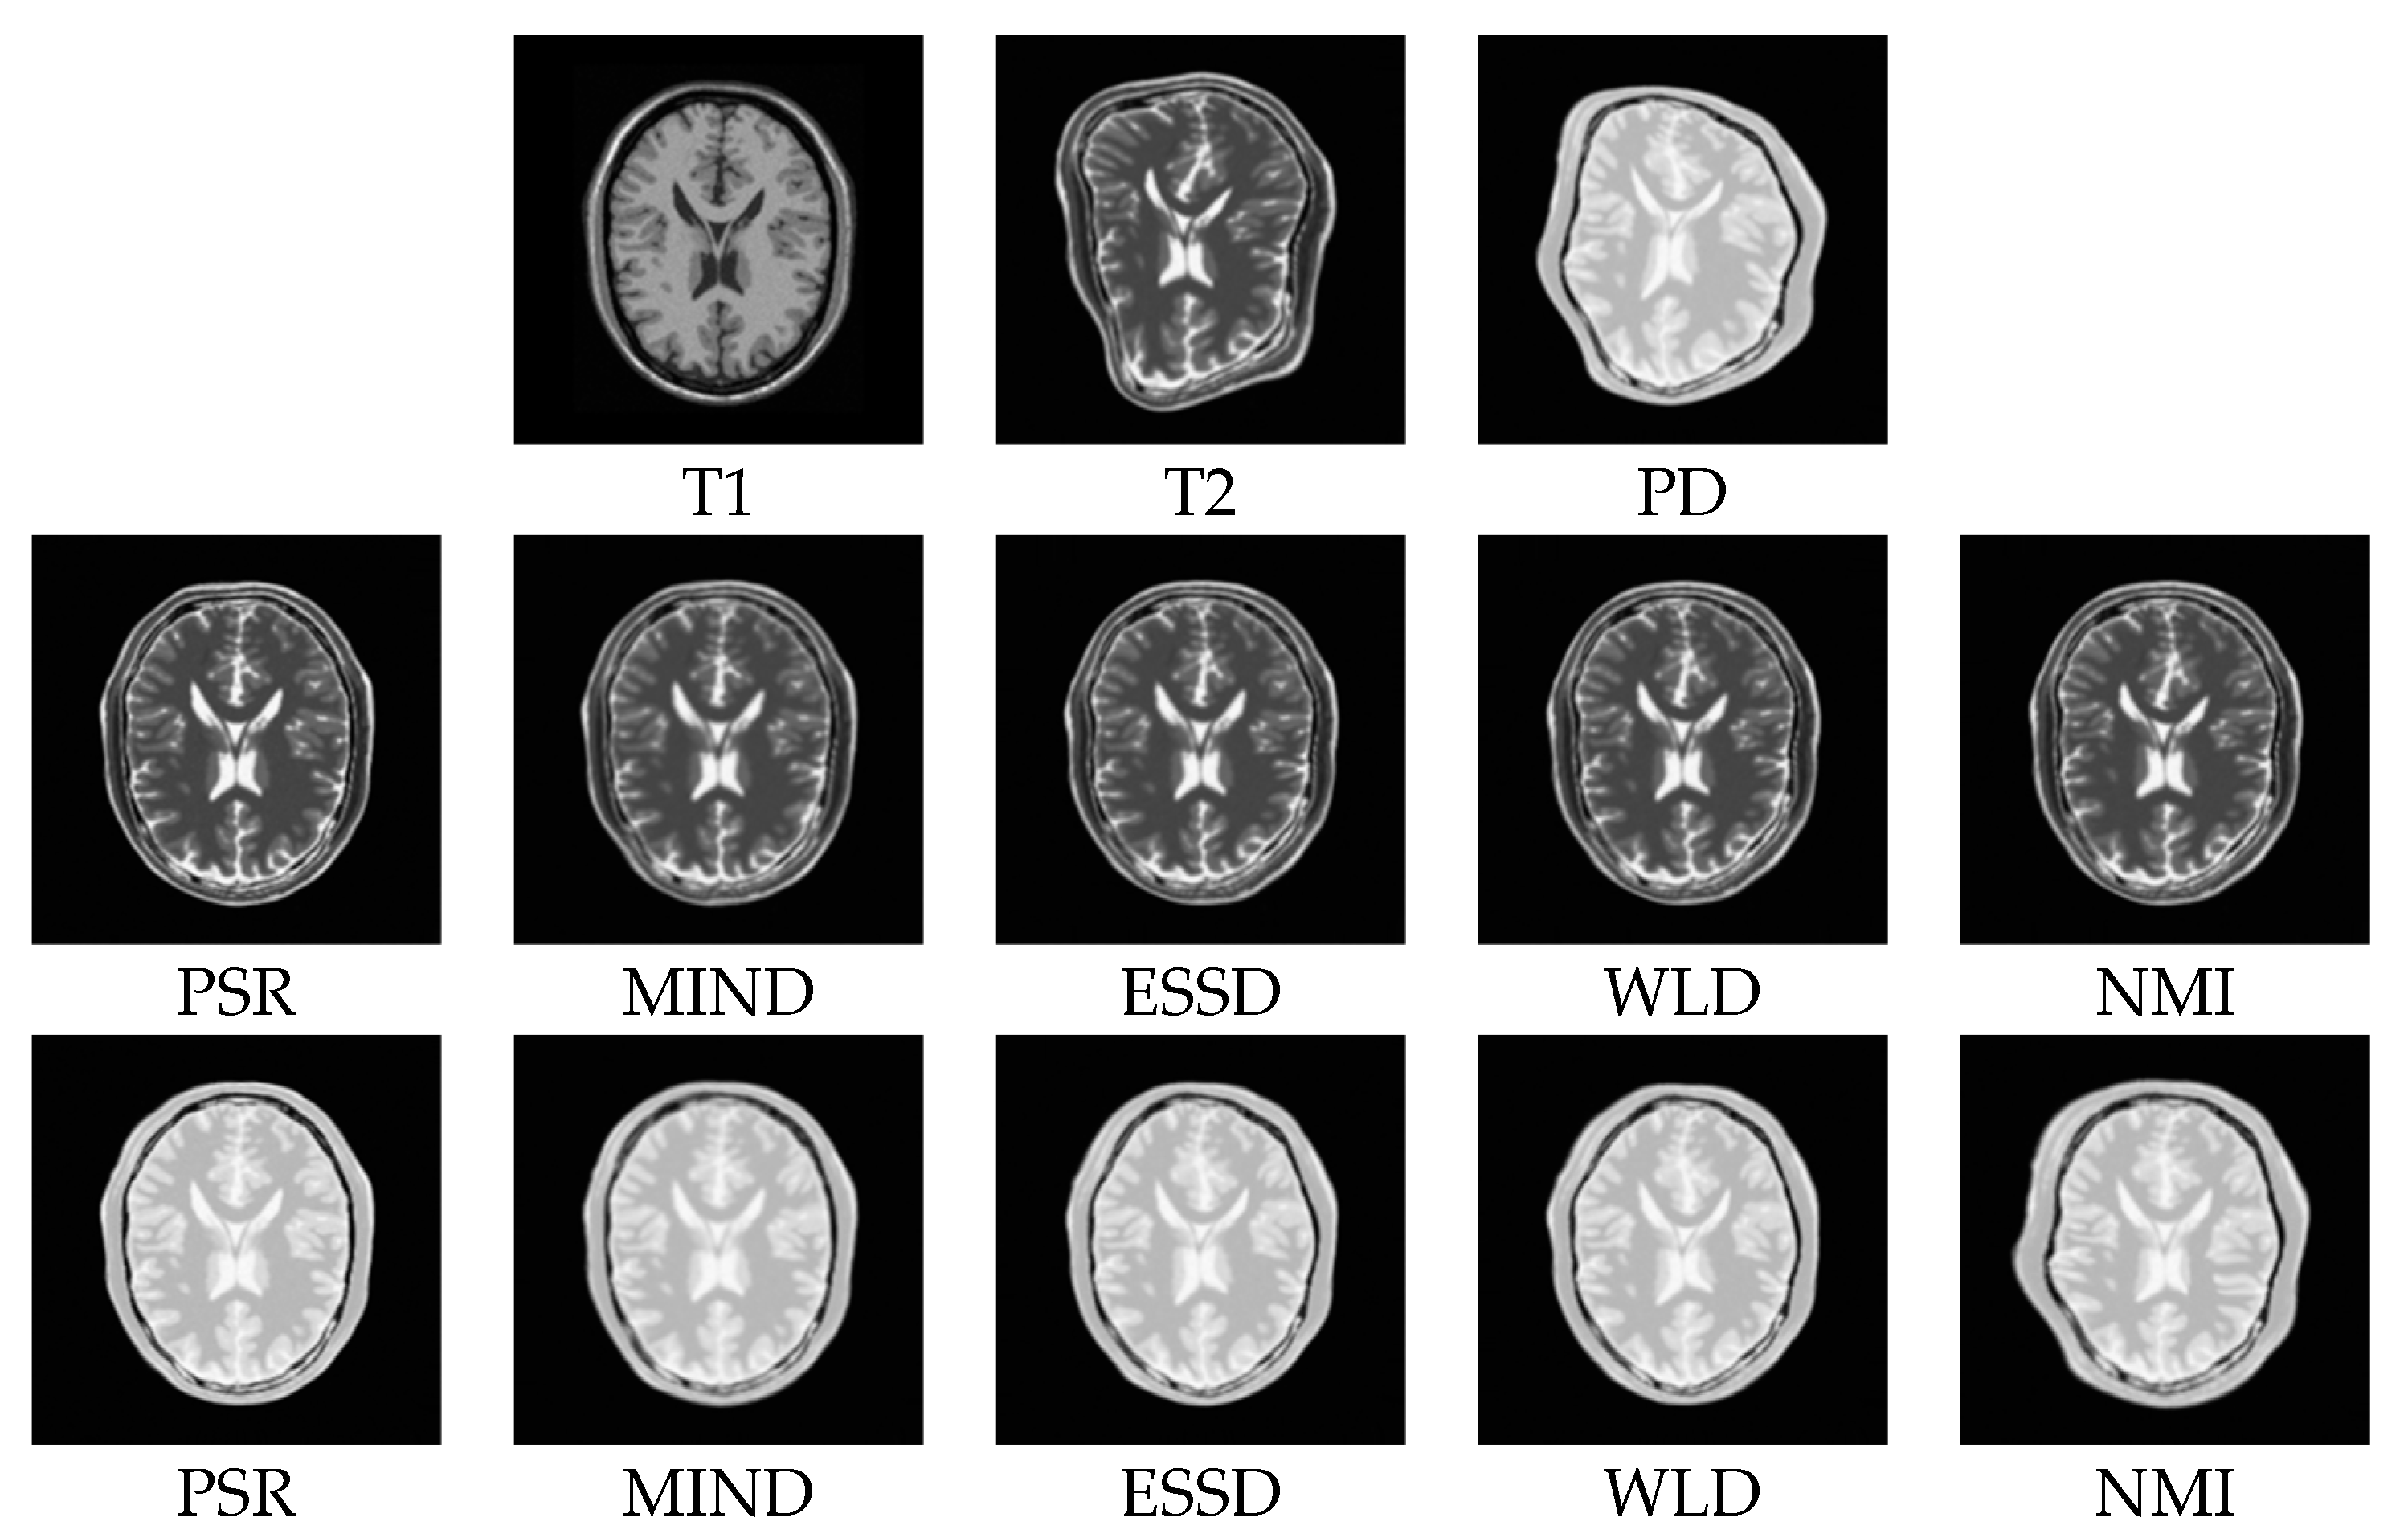

3.2.1. Test on the BrainWeb Dataset